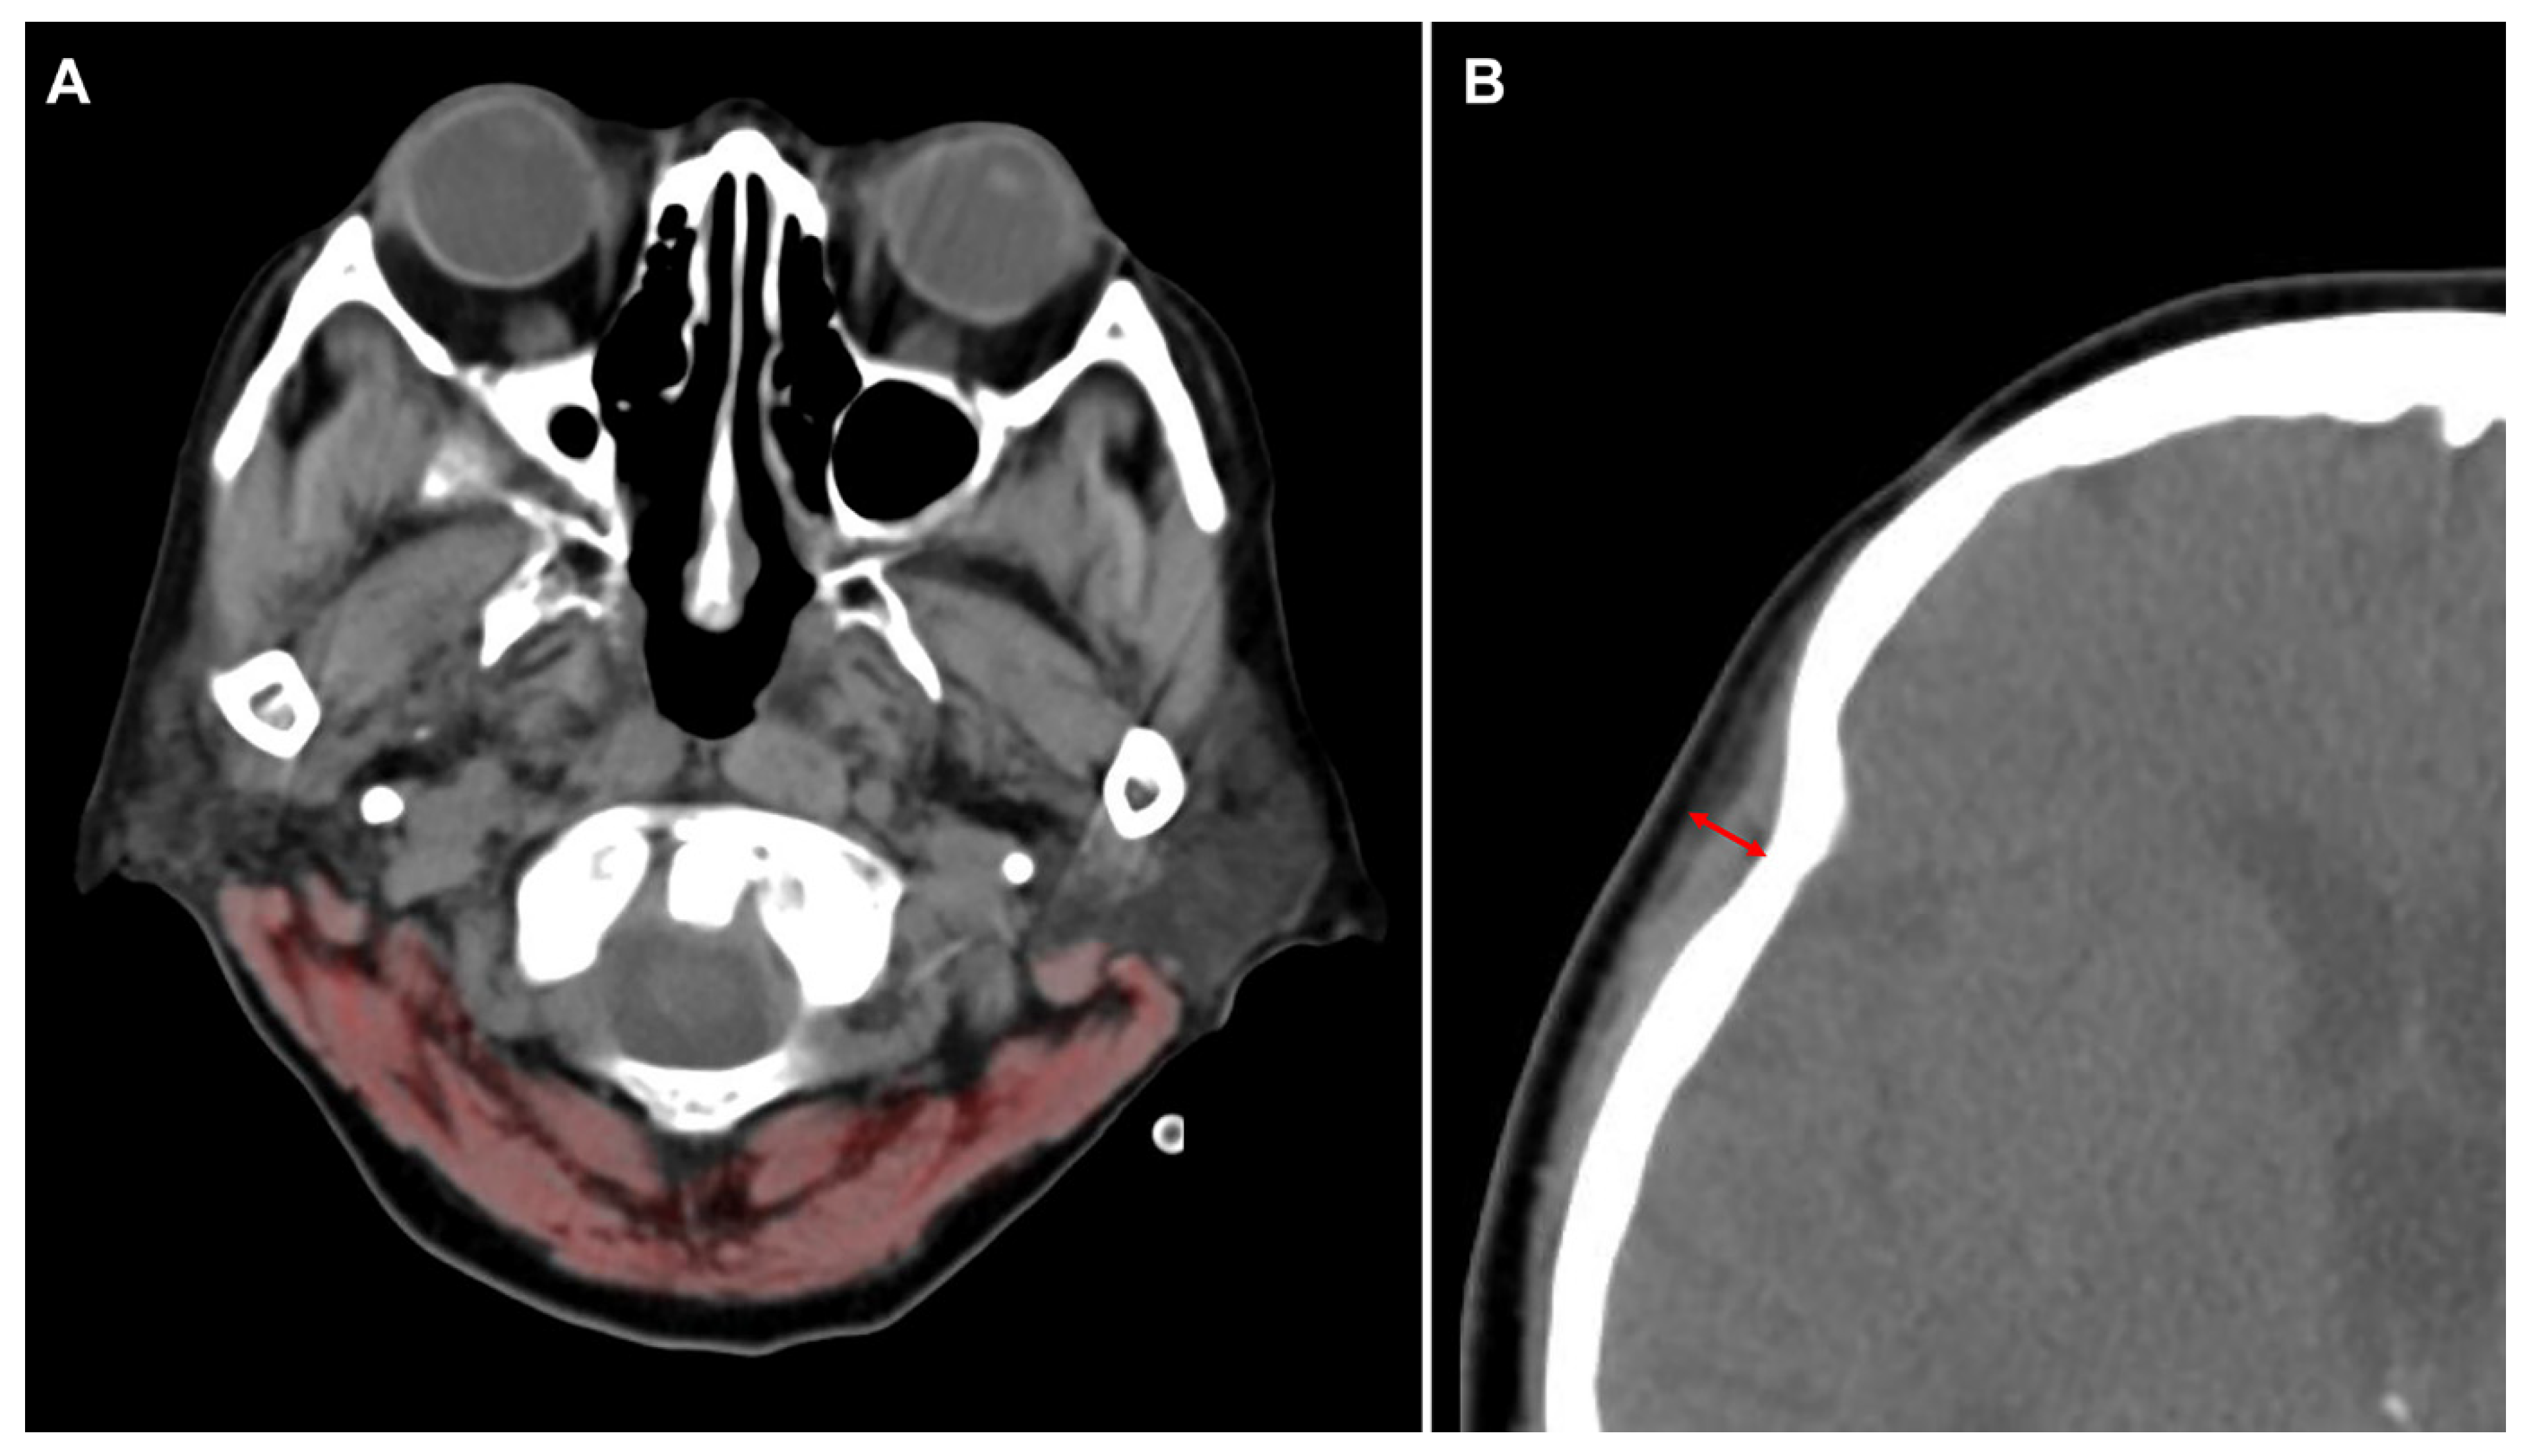

2. Materials and Methods

| CSA | cross-sectional area |

| CT | computed tomography |

| TMT | temporalis muscle thickness |